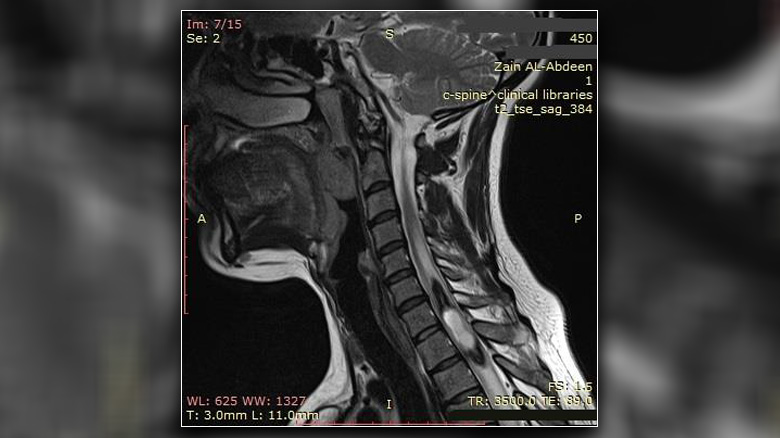

الحكمة – متابعة: أعلن مستشفى الإمام زين العابدين عليه السلام التابع للعتبة الحسينية المقدسة نجاح فريق الجراحة العصبية بإجراء عملية جراحية لرفع ورم من النخاع الشوكي لمريضة تعاني من “ألم رضي”.

وأفاد إعلام المستشفى ان المريضة راجعت المستشفى وهي تعاني من “ألم رضي” مع ضعف وتشنج الأطراف العلوية والسفلية, وعم القدرة على المشي.

وأضاف بعد إجراء الفحوصات لها تبين وجود ورم ضمن النخاع الشوكي, واجريت لها العملية وتم رفع الورم عبر مدخل خلفي في النخاع الشوكي باستخدام المجهر الالكتروني.

وأوضح إعلام المستشفى ان المريضة خرجت من العملية الجراحية بصحة جيدة, وتم تحويلها الى العلاج الفيزيائي، مشيرا الى ان نتائج تحليل عينة الورم أثبتت انه من نوع (Ependymoma) الذي يعرف بـ “ورم البطانة العصبية”.